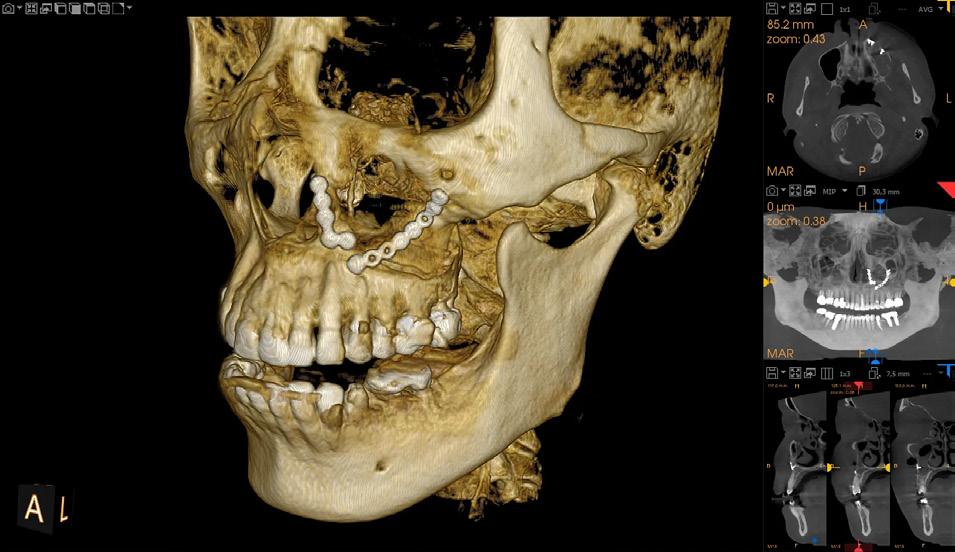

TrollBag for røntgensensorer

Supermyke trekk for sensorer og fosforplater. Helt uten lateks, lukt, smak og skarpe kanter. Lett å ta på og av, uten å ødelegge sensoren.

Tips: XL-trekket dekker både sensor og røntgenholder. En superenkel løsning som gjør hygienearbeidet mye enklere.

TrollBag for fosforplater

Supermyke poser for fosforplater.

Helt uten lateks, lukt, smak og skarpe kanter. Lett å ta på og av.

Leveres på rull i praktisk dispensereske.

-30% på alle TrollByte Kimera røntgenholdere

Gjelder til 15.11.2024

TrollByte Kimera finnes for alle typer sensorer, fosforplater og film. TrollByte enkel å bruke. Stive, robuste holdere som gir deg full kontroll når du skal ta bilde. Ingen artefakter på bildene fra holderen. Kan autoklaveres. Produsert av miljøvennligere bioplast - enda et viktig miljøtiltak.

Vi hjelper deg å finne riktig. Ring oss på telefon 66892050, på post@td.no eller på LiveChat på www.td.no

Kompakt og stiv holder for enkelt å ta bitewing. 3-pk røde holdere (var tidligere rød/sort). Før 1.499,-

Startsett m/én av hver TrollByte Kimera rød, gul og blå, samt siktering og bittblokk. 3-pk. Ønsker du bare én farge så velg et av settene nedenfor. Før 1.499,-

Stående holder for periapikale opptak. Siktering og bittblokk følger med. 3-pk blå. Før 1.499,-

1.049,3-pk

Periapikal liggende (gul)

Liggende holder for periapikale opptak og bitewing. Siktering og bittblokk følger med. 3-pk gul. Før 1.499,-

For indikatorbilder og sluttbilder. Sett med blå spesial endoholder for stående, og gul spesial endoholder for liggende opptak. Med rød og grønn endobittblokk og siktering. Finnes for alle sensorer, plater og film. Før 1.799,-

Hva betyr TrollByte-nummeret?

Eksempel: 4305/2905. 43=lengden på sensoren, 29=høyden, 05=tykkelse på sensor, målt i millimeter. 4305=mål for gul holder / 2905=mål for rød/blå holder. Mål gjerne din sensor. Vi hjelper deg gjerne!